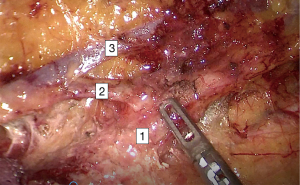

Participants in the skeletonization group underwent radical surgery. The vascular sheath was excised completely when cleaning the No. 253 lymph nodes, as shown in Figure 1. The left colic artery was preserved in all patients, while in the venation group, the vascular sheath was preserved when cleaning the No. 253 lymph nodes, as shown in Figure 2. The difference between the 2 groups was whether the vascular sheath was retained. All the operations were performed by the same group of surgeons.